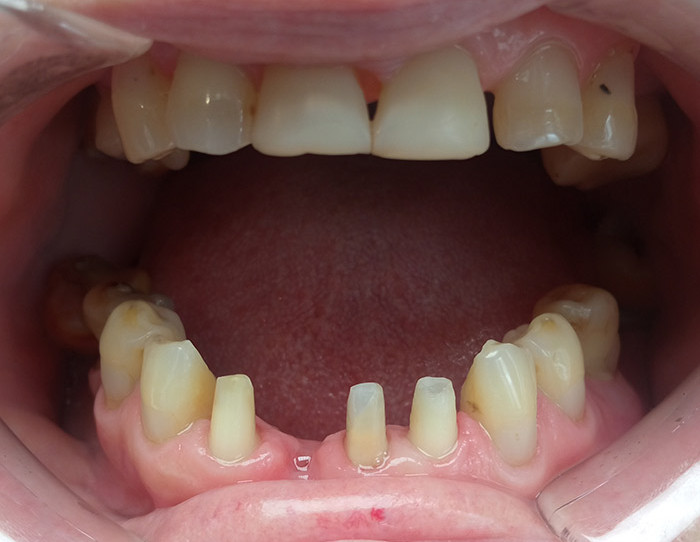

Рассмотрим пример изготовления мостовидного протеза.

Пациентке требуется срочно восстановить отсутствующий зуб, ее очень волнует внешний вид, зубы должны выглядеть «естественно».

Пациентке предложено восстановить отсутствующий зуб мостовидным протезом с из диоксида циркония. Для повышения эстетического эффекта влючить в протез еще один передний зуб. Таким образом получится 4 ровных красивых зуба.